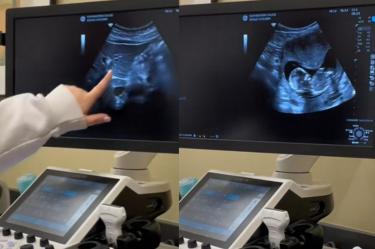

“Aquí está tu vesícula biliar, y ese es tu páncreas. Ahí está tu útero [...] ¿Qué es eso?”, se escucha en la publicación.

Al realizar la prueba, el monitor reflejaba algo fuera de lo común en el vientre de una de las estudiantes, pues se observaba un pequeño feto de varias semanas de embarazo.